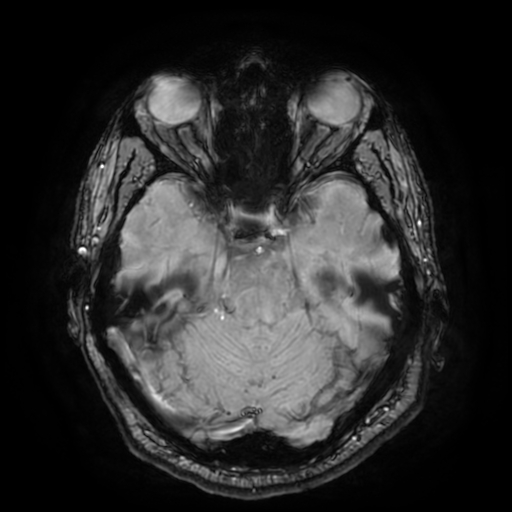

Gliose Pontina (nível máximo) 1 grande focos

SWI image 32

SWI #32

⚠️ ACHADO CRÍTICO:

Gliose Pontina (SWI #32) é um achado patognomónico de LAD Grau II. A presença de lesão no tronco cerebral confirma trauma axonal difuso moderado a grave.

🧠 Gliose Pontina

Pontine gliosis SWI

SWI #32: Gliose pontina (achado patognomónico LAD Grau II)

⚠️ CRÍTICO: Nenhum relatório volBrain menciona explicitamente gliose pontina, mas é visível em SWI.

• Gliose pontina (SWI #32) - Achado patognomónico